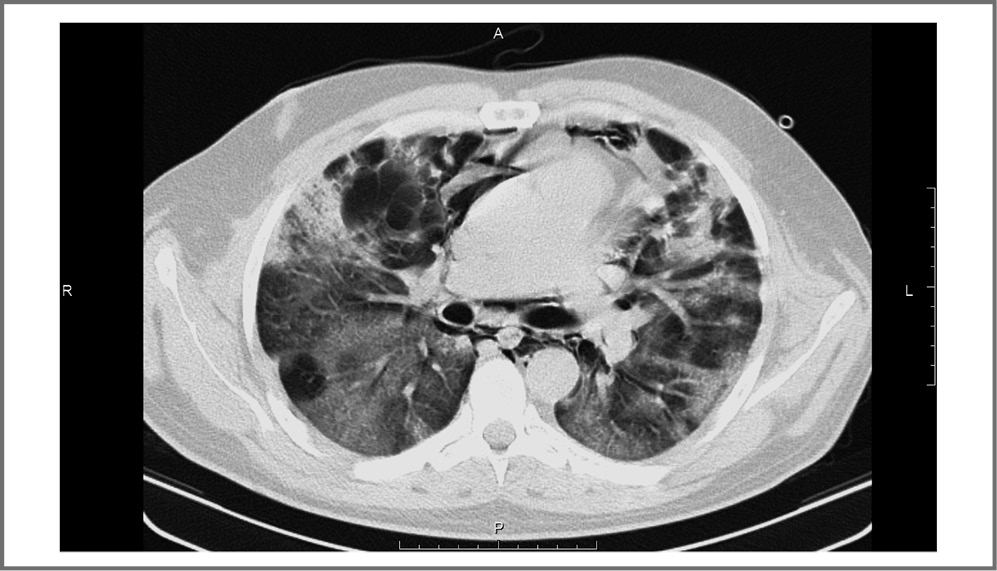

18.10.2021 (12-е сутки болезни) по данным СКТ ОГП объем поражения увеличился до 75% (рис. 3), в этот же день с целью обеспечения адекватной респираторной поддержки пациент помещен в отделение интенсивной терапии. В связи с нарастанием ДН подключена высокопоточная оксигенотерапия 80% О2 – 50 л/мин, принято решение о проведении пульс-терапии метилпреднизолоном (1000 мг/сут в течение 3 дней) с переводом на метилпреднизолон в таблетированной форме в суточной дозе 32 мг/сут.

Рис. 3. Компьютерная томограмма ОГП на уровне бифуркации трахеи от 18.10.2021. Определяется выраженная отрицательная динамика за счет появления по всем легочным полям многочисленных зон интерстициальной инфильтрации. Объем поражения ~75%.

Fig. 3. CT of the chest at the level of the tracheal bifurcation from 10.18.2021. A pronounced negative dynamics is determined due to the appearance of numerous zones of interstitial infiltration in all lung fields. Damage volume ~75%.